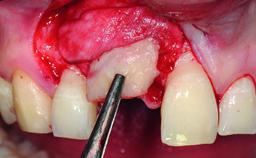

Bone Augmentation Horizontal|Simultaneous

Augmentation Materials Autogenous chips|Xenogenous|Membrane

Bone Volume Deficient horizontally, allowing simultaneous augumentation